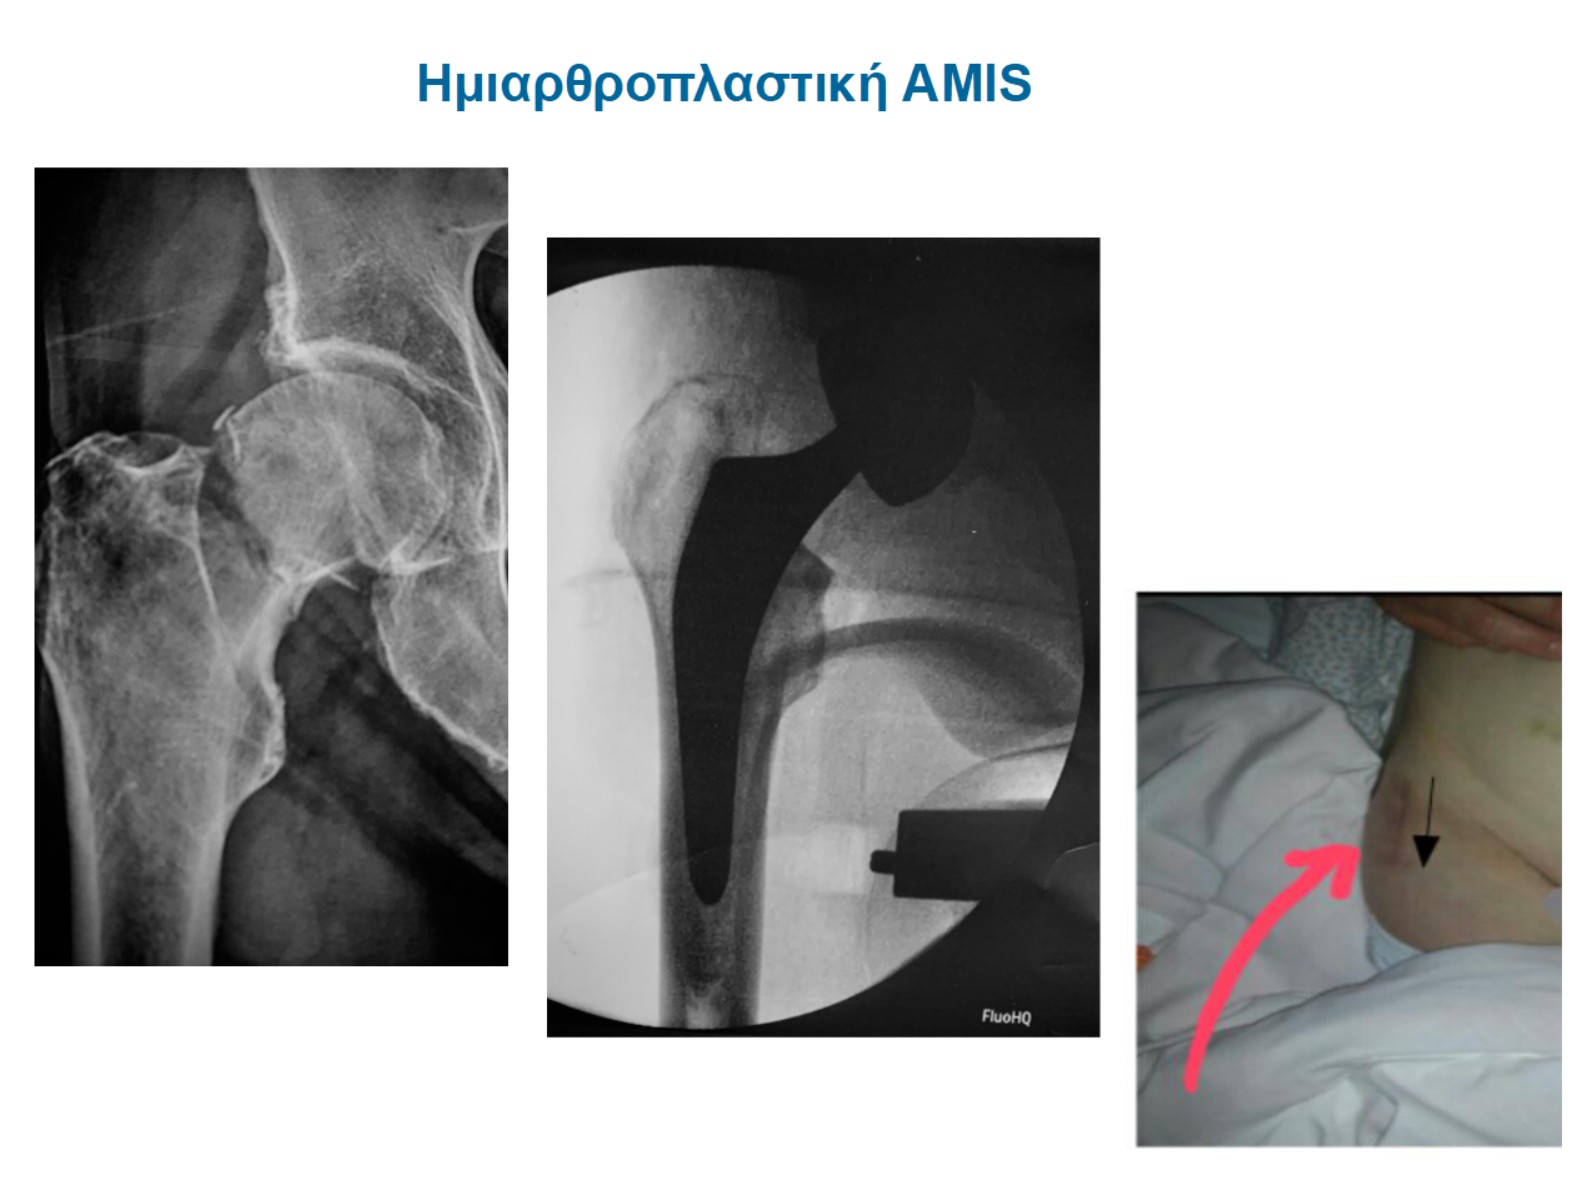

Είναι γνωστό στην ορθοπαιδική κοινότητα ότι το διατροχαντήριο κάταγμα είναι το πρώτο “εκπαιδευτικό” κάταγμα, αυτό στο οποίο οι νέοι γιατροί μαθαίνουν τις αρχές της χειρουργικής Τέχνης. Είναι λοιπόν ένα εύκολο και απλό κάταγμα; η απάντηση είναι σαφώς και όχι. Γίνεται απλό όταν υπάρχει βαθιά γνώση των σταδίων της επέμβασης και δυνατότητα αντιμετώπισης δυσκολιών που θα προκύψουν στην πορεία, παράδειγμα:

(εικόνα 8, δύο παραδείγματα υπερηλίκων ασθενών που εξαιτίας της μεγάλης συντριβής δεν επετέυχθη κλειστή ανάταξη. Ήταν αναγκαίο λοιπόν να τοποθετηθούν οστικά “σύρματα” με σκοπό να συκρατηθούν τα οστικά τεμάχια: μια τεχνική απαιτητική που απαιτεί μεγάλη εμπειρία)

Στην εικόνα 9, παρουσιάζεται η ιδανική τοποθέτηση του κεντρικού κοχλία στην κεφαλή του μηριαίου. Η ασθενής φόρτισε ελεύθερα από την πρώτη μέρα χωρίς φόβο αποτυχίας της οστεοσύνθεσης (βίντεο).

Στην εικόνα 10, ήλος που τοποθετήθηκε εξ’αρχής σε λάθος θέση, χωρίς πρώτα να έχει επιτευχθεί ικανοποιητική ανάταξη στο κάταγμα: η κινητοποίηση οδήγησε σε αποτυχία στο πρώτο μετεγχειρητικό τρίμηνο. Αντιμετωπίστηκε από την κλινική μας με οστεσύνθεση και αρθροπλαστική.